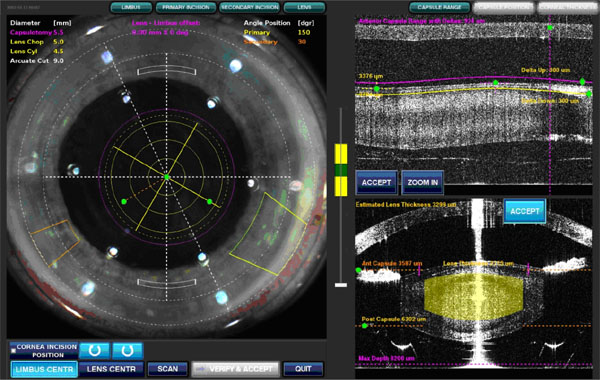

1. 高科技 3D 影像導引,更精準更安全

- 以 3D 即時電腦斷層掃描建構眼部結構

- 精確鎖定角膜、前囊、水晶體及囊袋位置

- 協助醫師即時掌握手術狀況,特別在 高難度白內障(硬核、瞳孔小、複雜病例)更能提升安全性